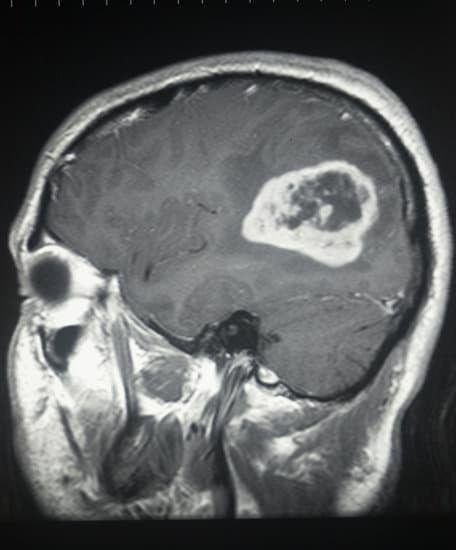

뇌종양의 진단

뇌종양의 진단은 주로 영상 진단 방법을 통해 이루어집니다.

자기공명영상(MRI)과 컴퓨터단층촬영(CT) 스캔이 가장 일반적으로 사용되며, 이를 통해 종양의 위치, 크기, 영향을 받는 조직의 범위를 평가할 수 있습니다.